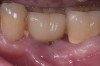

Fig 7. Eight weeks after nonsurgical treatment that involved scaling of the area, which removed cement, and irrigation with an anti-inflammatory hydrogel, the area is healthy. No BOP is present, purulence is absent, and probing depths have been reduced to 4 mm as a result of the reduction in inflammation.

Figure 7